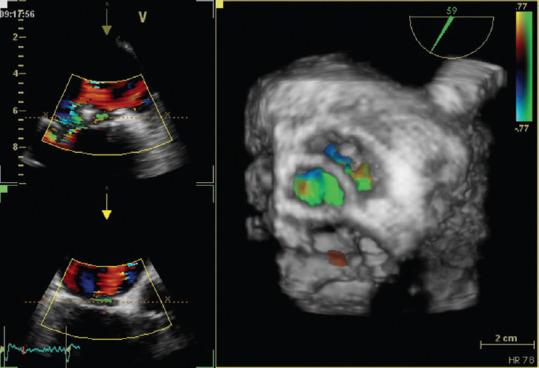

Infective endocarditis (IE) diagnosis is based on a clinical suspicion supported by consistent microbiological and instrumental data. Evidence of involvement of cardiac valves (native or prosthetic) or prosthetic intracardiac material is a major diagnostic criterion of IE. Transthoracic echocardiography (TTE) is the initial technique of choice for the diagnosis while transesophageal echocardiography (TEE) is recommended in patients with an inconclusive or negative TTE, in patients with high suspicion of IE, as well as in patients with a positive TTE, in order to document local complications. Repeating TTE and/or TEE should be considered during follow-up of uncomplicated IE, in order to detect new silent complications and monitor vegetation size. In the setting of IE, the role of three-dimensional (3D) TEE is increasing; in fact, this technique has also been shown to be useful for the diagnosis of IE and its complications as it allows to obtain infinite planes and volumetric reconstructions. In this review, we will describe the usefulness of 3D-TEE and its added value in the management of IE.

感染性心内膜炎(IE)的诊断基于临床怀疑,并辅以一致的微生物学和影像学数据。心脏瓣膜(天然或人工)或人工心内材料受累的证据是IE的主要诊断标准。经胸超声心动图(TTE)是诊断的首选初始技术,而对于TTE结果不确定或为阴性的患者、高度怀疑IE的患者以及TTE结果为阳性的患者,推荐行经食管超声心动图(TEE)检查,以记录局部并发症。对于无并发症的IE患者,在随访期间应考虑重复进行TTE和/或TEE检查,以便发现新的隐匿性并发症并监测赘生物大小。在IE的情况下,三维(3D)TEE的作用越来越大;事实上,该技术也已被证明对IE及其并发症的诊断有用,因为它可以获得无限平面和容积重建。在本综述中,我们将描述3D-TEE的实用性及其在IE管理中的附加价值。